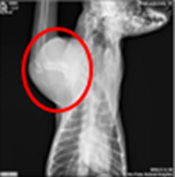

吉祥雖有持續接受藥物治療,右前肢無力跛行無明顯改善,於癌識優®檢測結果為陽性兩個月後,上膊骨位置於短時間內快速腫大,X光檢測發現新生骨贅、軟組織增生及疑似腫瘤團塊,經組織病理診斷為骨肉瘤。

X光影像檢測,軟組織腫脹、骨贅新生明顯